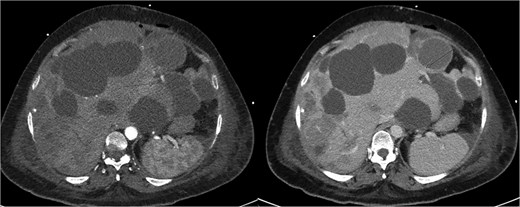

Posthumously, the resected liver histology returned with appearances consistent with epithelioid angiosarcoma with deep invasion past the liver capsule (Fig. 3).

Histopathology of resected liver specimen. (A) Epithelioid angiosarcoma involving liver parenchyma with broad areas of necrosis (4× magnification). (B) Round to polygonal epithelioid tumour cells with prominent nucleoli, and associated red blood cells and neutrophils (40× magnification). (C) ERG immunohistochemistry staining tumour nuclei (20× magnification). (D) Polycystic liver disease, numerous cysts, some with von Meyenburg complexes (arrow) (10× magnification).